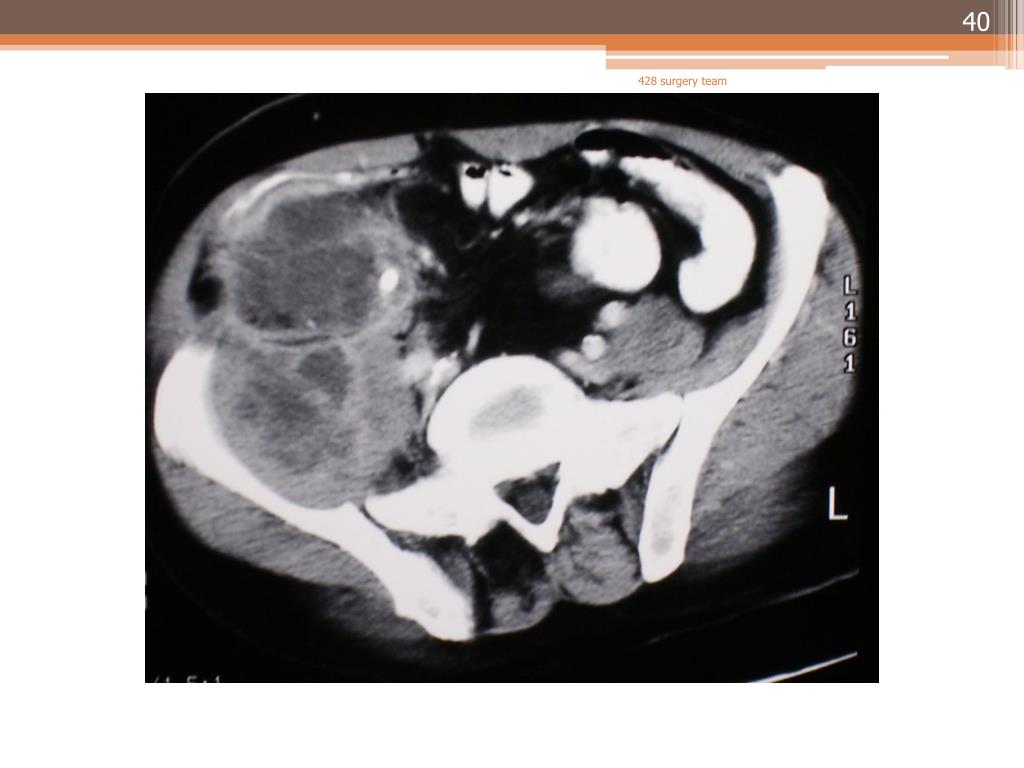

40. 428 surgery team